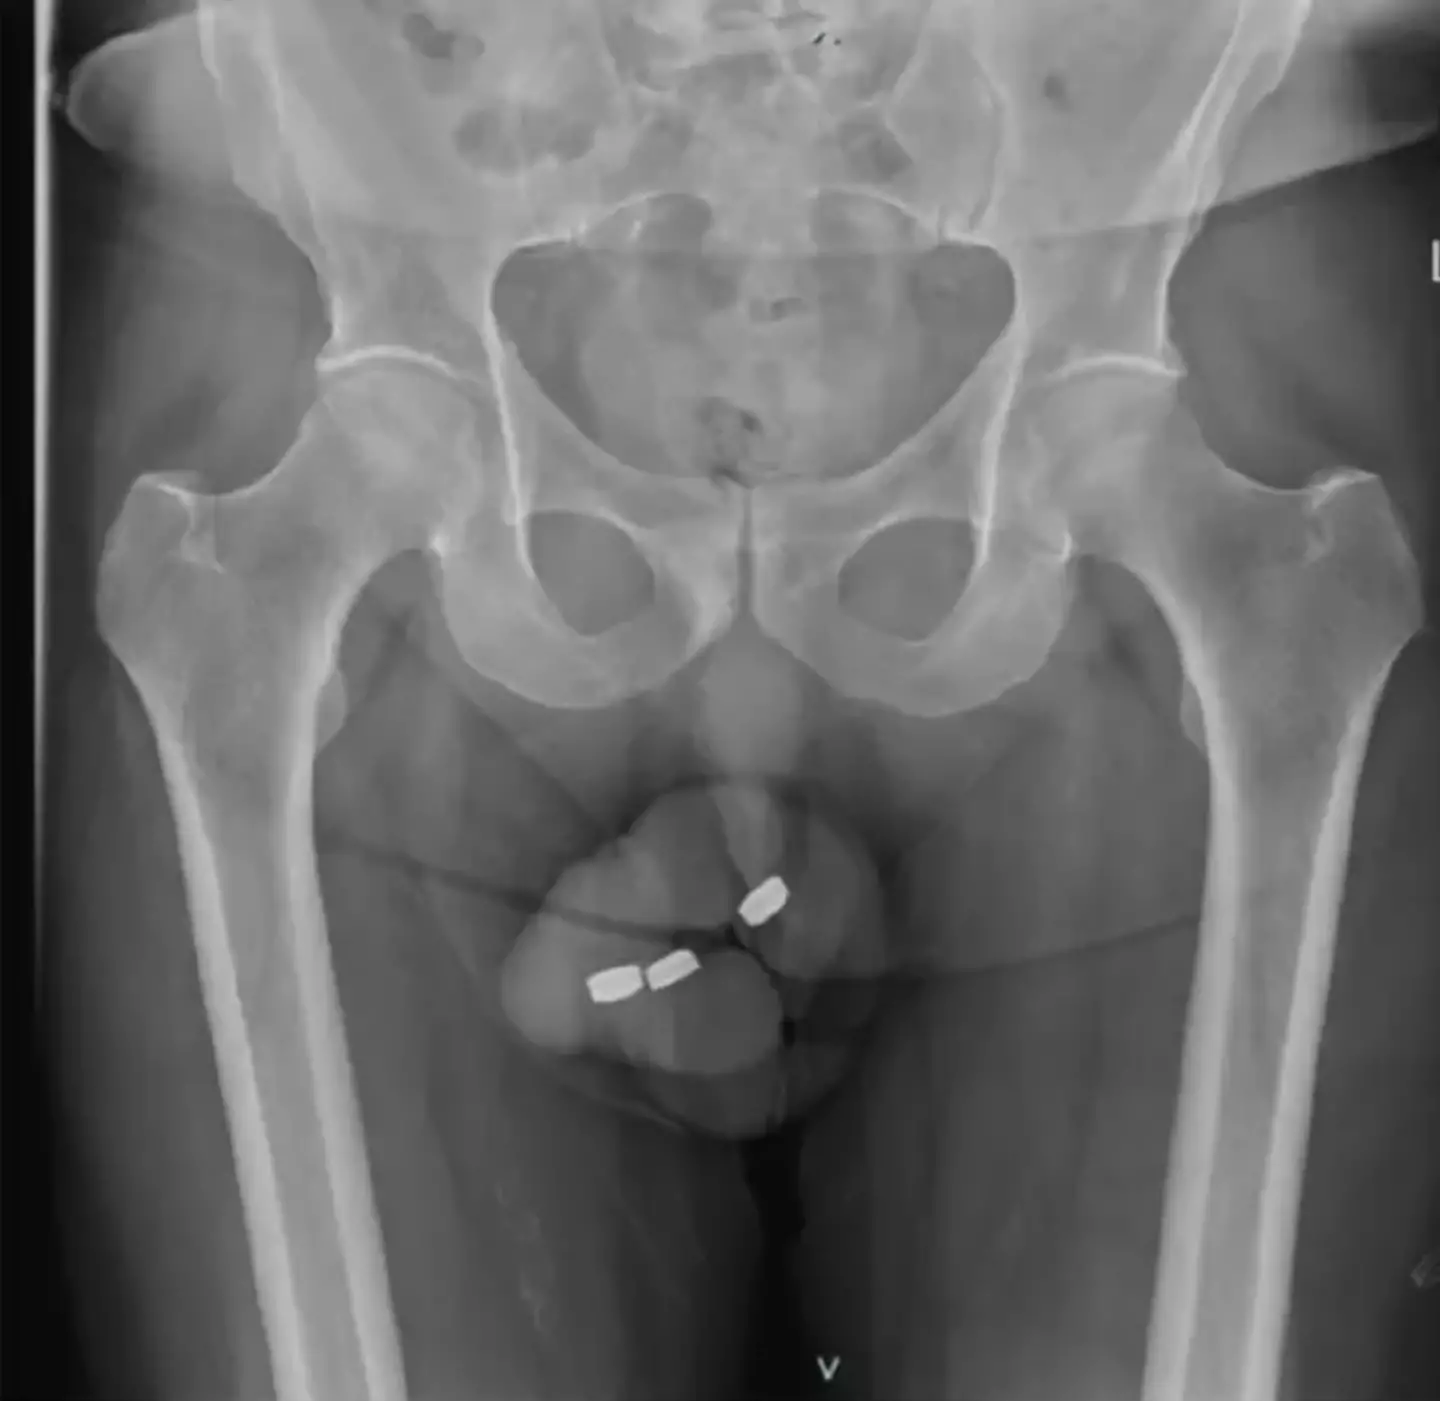

The Australian-born man horrifyingly needed urgent urethra surgery after jamming three button-style batteries into his penis.

During the man's recent episode with batteries, they had 'migrated more proximally within the penile urethra' after a few unsuccessful attempts to remove them.

After a rather embarrassing mishap, the man ended up in the medical department with 'moderate penile pain, severe paraphimosis and obstructive urinary symptoms'.

However, the man had to wait 24 hours to receive much-needed medical attention, forcing doctors to quickly remove the foreign objects once he had been attended to.

But after resorting to forceps, they were finally able to get the batteries out.